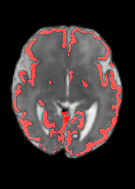

Fetal cortical plate segmentation is essential in quantitative analysis of fetal brain maturation and cortical folding. Manual segmentation of the cortical plate, or manual refinement of automatic segmentations is tedious and time-consuming. Automatic segmentation of the cortical plate, on the other hand, is challenged by the relatively low resolution of the reconstructed fetal brain MRI scans compared to the thin structure of the cortical plate, partial voluming, and the wide range of variations in the morphology of the cortical plate as the brain matures during gestation. To reduce the burden of manual refinement of segmentations, we have developed a new and powerful deep learning segmentation method. Our method exploits new deep attentive modules with mixed kernel convolutions within a fully convolutional neural network architecture that utilizes deep supervision and residual connections. We evaluated our method quantitatively based on several performance measures and expert evaluations. Results show that our method outperforms several state-of-the-art deep models for segmentation, as well as a state-of-the-art multi-atlas segmentation technique. We achieved average Dice similarity coefficient of 0.87, average Hausdorff distance of 0.96 mm, and average symmetric surface difference of 0.28 mm on reconstructed fetal brain MRI scans of fetuses scanned in the gestational age range of 16 to 39 weeks. With a computation time of less than 1 minute per fetal brain, our method can facilitate and accelerate large-scale studies on normal and altered fetal brain cortical maturation and folding.